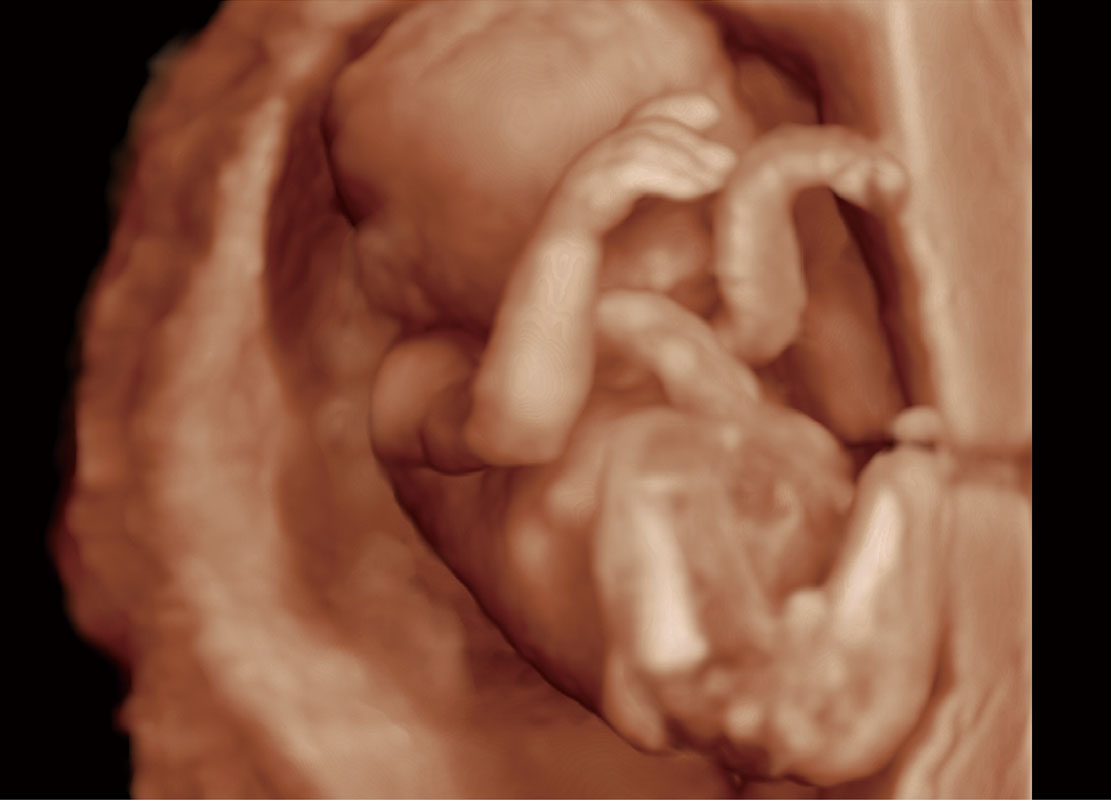

P60在胎儿早孕期超声筛查中为您带来优异的图像质量。

早孕-胎心

高分辨率容积成像-早孕胎儿

光影成像-孕囊